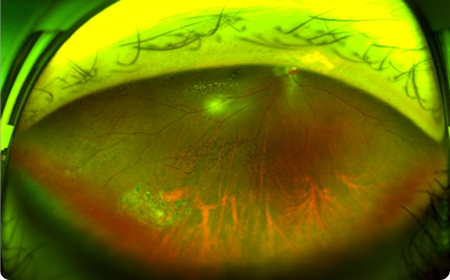

Deep-Scan

주변부 열공/변성 포착

망막 박리 위험이 높은 고도근시, 문제는 항상 ‘주변부’에 숨어 있습니다.

대학병원급 광각 장비로 보이지 않는 사각지대까지 스캔합니다.

OPTOS–Daytona

무산동 광각 안저 촬영기

무산동 상태에서 전체 망막의 200도

(약 80%)범위의 촬영이 가능해 망막의 중심부와 주변부를 빠르게 확인할 수 있습니다.

평소에 인지 하지 못하던 망막주변부의 질환

(망막열공,변성 등)에 대한 조기 진단이 가능합니다.